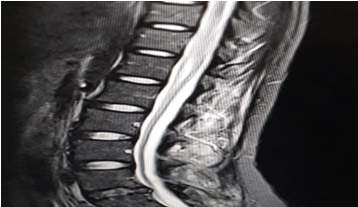

A cerebral MRI was performed to show the appearance of right fronto-temporal meningoencephalitis and left fronto-temporo parietal meningoencephalitis with a left external lenticulocapsular ischemic lesion (figure 2). Herpes PCR was performed in the CSF supplemented with expert tuberculosis gene on CSF which showed the presence of mycobacteria DNA of the tuberculosis complex. Chest X-ray was normal, with BK sputum negative. The treatment was completed by corticotherapy (product and dose at d4) and withdrawal of antivirals and C3G. The evolution was favourable at two weeks of treatment with disappearance of the HTIC syndrome and the beginning of recovery of her deficit with type mobilization of the toes and sensitivity, then the patient was transferred to the infectious disease department.

Figure 2: Appearance of Right Front temporal and Left Front temporal Parietal Meningoencephalitis with Left External Lenticulocapsular Ischemic Lesion